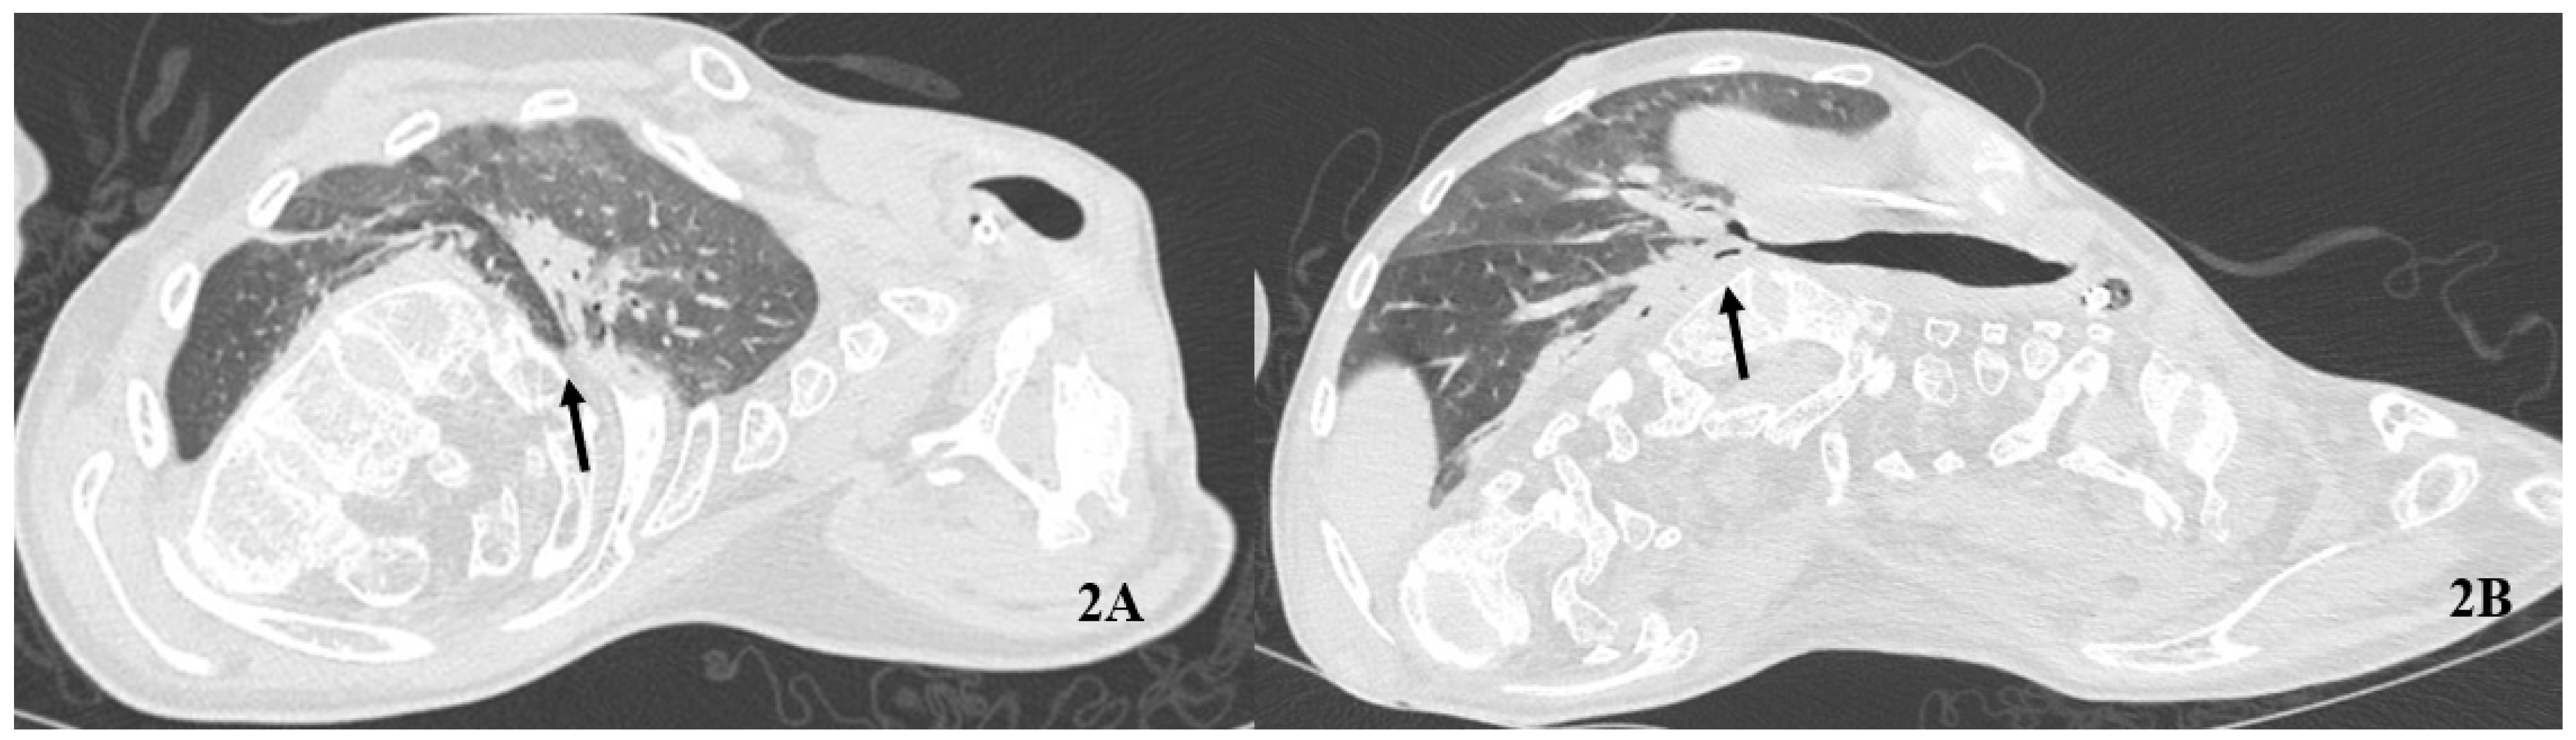

A gradual but stable improvement in gas exchange was observed over 14 days. pO2 was higher during IAPV plus HFNC compared to HFNC alone. pH and pCO2 constantly improved after the IAPV sessions (Table 1). The following HRCT confirmed a substantial resolution of most consolidation bilaterally (Figure 2).

Figure 2.

Follow-up computed tomography of the chest. The arrows indicate the sub-total resolution of consolidations at hilum (A) and the right lower lobe (B).